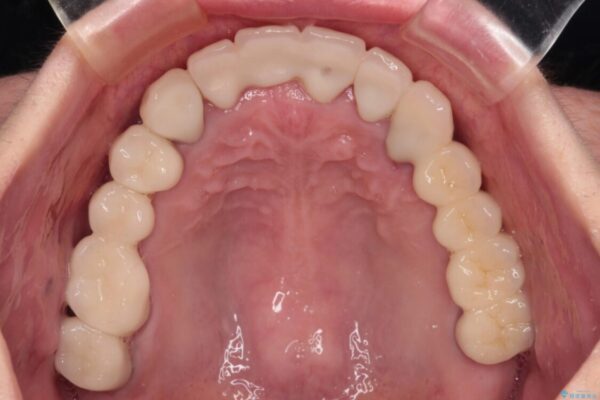

治療前

• 放置したインプラントとインビザライン 全顎リカバリー治療 治療前画像